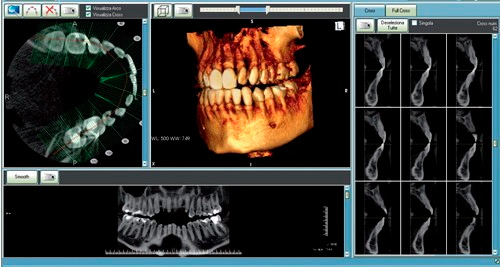

Компьютерная томография

Основное отличие КТ от классического рентгена заключается в качестве получаемого изображения. На результатах компьютерной томографии зубов видны даже незначительные изменения в структурах ткани. Эта процедура позволяет выявить патологические процессы на начальной стадии, что помогает вовремя предупредить стремительное развитие заболевания и подобрать оптимальные методы лечения. В стоматологии безопасная компьютерная томография челюсти проводится на аппарате Ortophos SL (Sirona, Германия). Аппарат позволяет получать 3D снимки с высоким разрешением.

КЛКТ (конусно-лучевая компьютерная томография) проводится для следующих областей:

- челюстно-лицевой отдел черепа;

- височно-нижнечелюстные суставы;

- верхней и нижней челюсти;

- пазухи носа и их придатки;

- прицельное сканирование (одна анатомическая единица).

3д снимок зубов или челюсти может потребоваться при выборе метода протезирования для оценки количества и качества костной ткани, для выявления точных размеров и локализации новообразований (кист, гранулем и др.). КЛКТ челюсти является безальтернативным методом диагностики при необходимости установки дентальных имплантов.

По сравнению с иными методами рентгенологической диагностики, компьютерная томография (КТ) челюсти обладает абсолютными преимуществами. Все дело в том, что при обычной рентгенодиагностике зубов врач может получить только плоское – двухмерное изображение сканируемого объекта, а после получения панорамного 3D-снимка зубов врач видит трехмерный объект, что позволяет улучшить качество исследования.

Аппарат Planmeca ProMax ® 3D Mid соответствуют множеству диагностических требований имплантологии, эндодонтии, пародонтологии, ортодонтии, стоматологической и челюстно-лицевой хирургии и анализа височно-нижнечелюстного сустава. Это также отличный инструмент для диагностики уха, верхнечелюстных пазух и заболеваний дыхательных путей.

Данные 3D-исследования записываются на диск, который предоставляется пациенту, и в дальнейшем любой врач-стоматолог имеет возможность просмотреть и изучить их на обычном компьютере в условиях своей клиники.

Высочайшая информативность такого вида исследования в разы повышает эффективность последующего лечения, поскольку позволяет не только изучить мельчайшие нюансы строения зубочелюстной системы, но и выявить на ранней стадии возможные патологические изменения.

Областью исследования может быть как вся челюстно-лицевая область, для чего необходимо сделать панорамный снимок зубов, так и отдельные сегменты, требующие изучения. В этом случае выполняется снимок интересующего участка зубочелюстной системы.